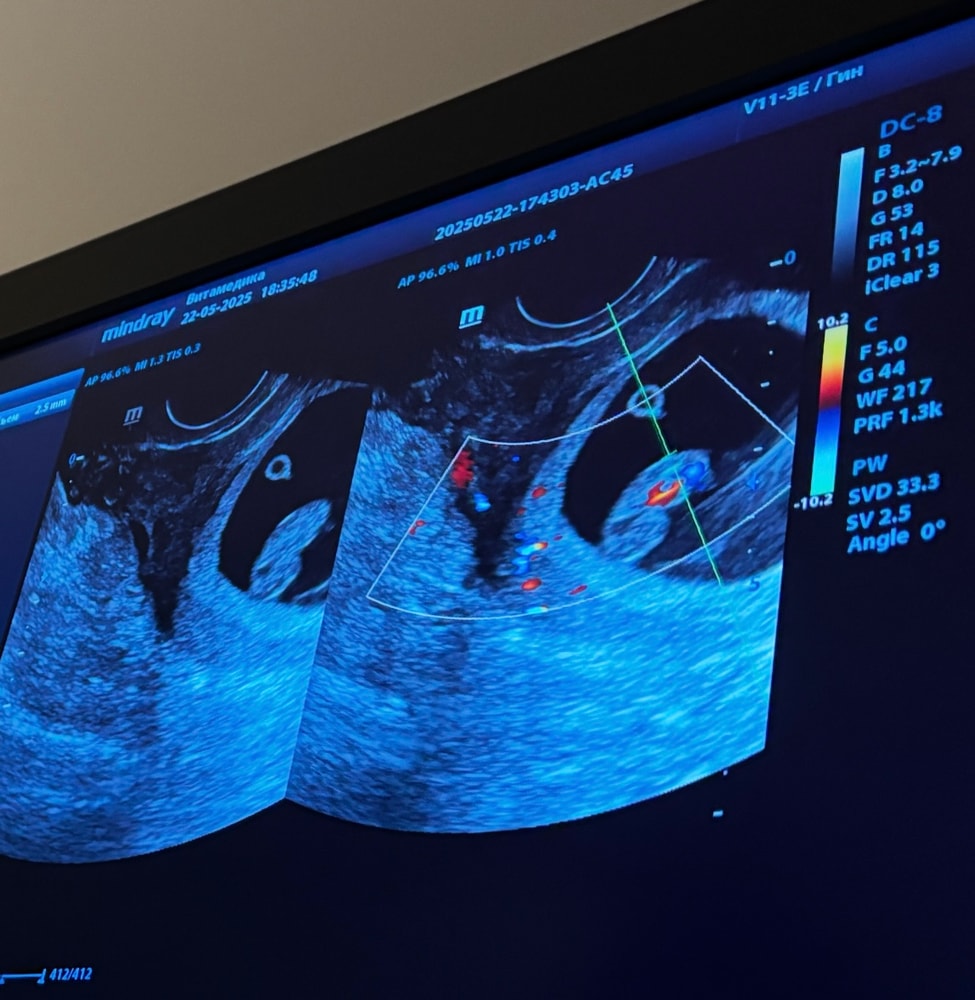

Диана, Изображение

Леся Леся, узи делали через живот ?

Леся Леся, если вагинально то мальчик ,через живот девочка